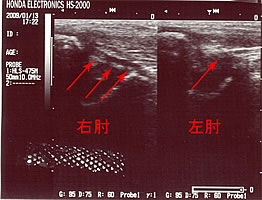

写真(↓)の右肘(患側)の矢印の先に、斜め(左上から右下にかけて)に黒い帯が確認できますでしょうか。肘関節の内側側副靱帯MCL(尺側側副靭帯UCL)です。

左肘の健側は、少し写りがよくありませんが、帯状にはなっておりません。

黒く帯状に描出されているのは、肘の内側側副靱帯の腫脹(腫れている)を示しています。

断裂してはいませんので、腫脹が治まるまで局所の安静および加療となります。